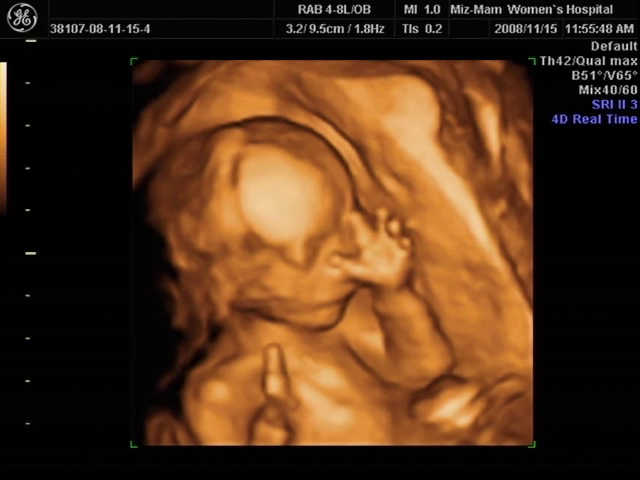

081115_별이입체초음파캡쳐 (4).jpg

첫째 아이 초음파 사진